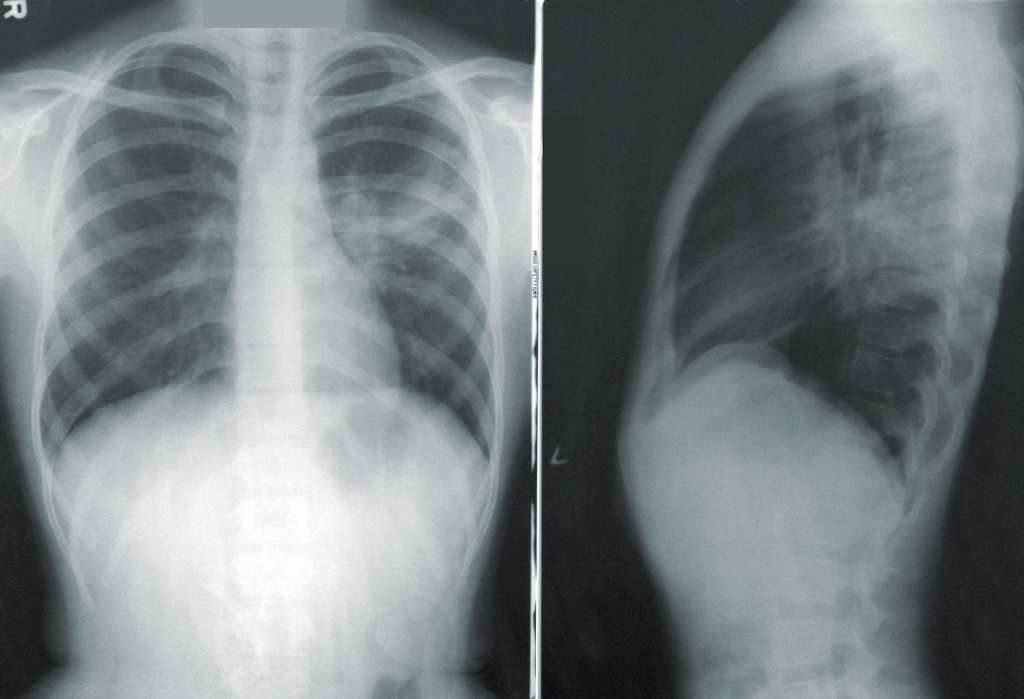

“ To confirm lung inflammation, a chest X-ray is required. In this, what we analyze is that if we see that the entire lung is black, it means that we only have air, but if we see white lesions that can be localized or patched in both lungs, it tells us about inflammation,” explains Ábalos.